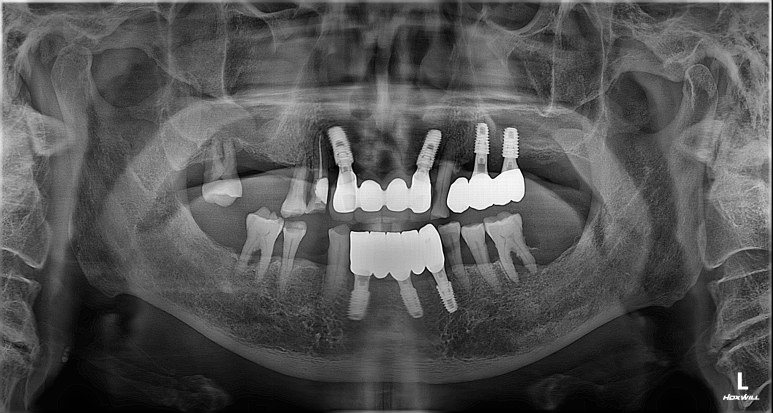

앞니는 대화하거나 웃을 때 가장 먼저 노출되는 부위이며, 식사의 첫 단계를 담당하는 중요한 치아입니다. 환자분의 우선순위를 존중하여, 1차적으로 하악 전치부에 임플란트 식립을 선행하였습니다. 이를 통해 환자분이 가장 크게 느끼던 심미적 결손과 앞니 저작의 불편함을 빠르게 해소하는 데 집중했습니다.

앞니 부위의 수술이 안정적으로 진행된 후, 어금니 저작 기능 회복을 위해 좌측 대구치 부위의 수술을 이어서 진행했습니다.

방사선 사진에서 확인할 수 있듯, 좌측 상악 어금니 부위는 치아가 빠진 지 오래되어 잔존 치조골(잇몸뼈)이 매우 얇아진 상태였습니다. 임플란트를 단단하게 고정할 뼈가 부족했기 때문에, 위턱뼈 속의 빈 공간인 상악동 막을 조심스럽게 들어 올리고 그 공간에 뼈를 채워 넣는 '상악동 거상술'을 시행했습니다.

수술의 효율성을 높이고 환자분의 내원 횟수를 줄이기 위해 상악동 거상술과 임플란트 픽스처 식립을 동시에 진행했습니다.